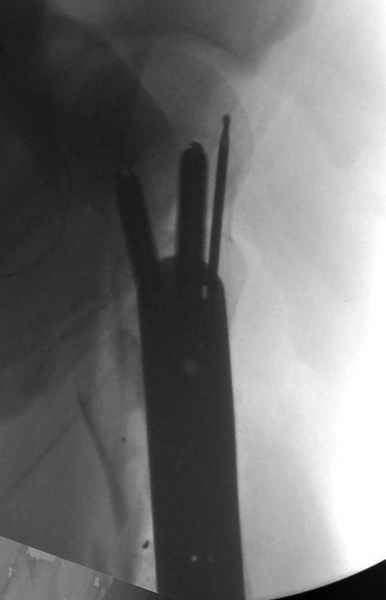

Из всех типов фиксации взяли малоинвазивную технику мостовидной пластиной, использовали Locking проксимальную Synthes пластину.